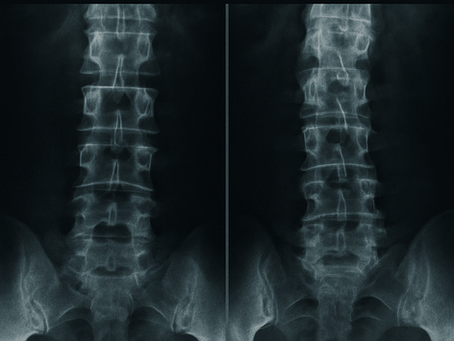

What is Ankylosing Spondylitis?

Ankylosing Spondylitis causes spinal stiffness and pain. Learn signs, nursing care, and why movement matters in managing this condition.